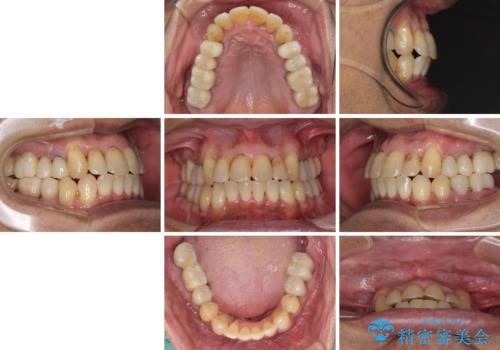

歯槽骨の再生治療を行ったため、外科処置後の静置期間がながくなり、4年弱の治療期間となりました。

初診来院時には矯正治療を行うことは想像していなかったようで、治療後には咬みやすさだけでなく、前歯が大変審美的に仕上がり、患者様には大変満足していただきました。